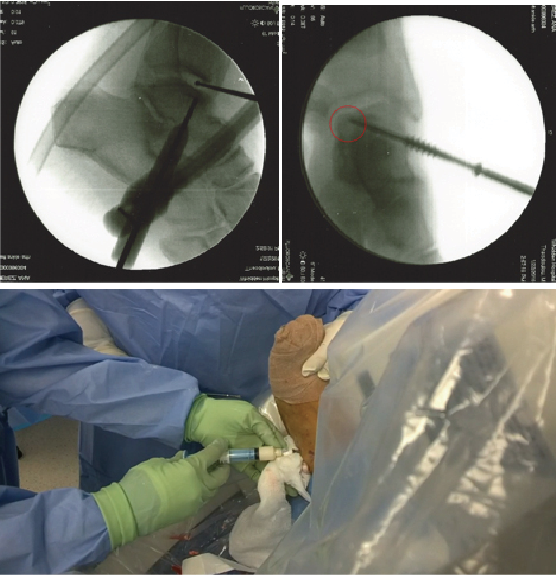

Wylie and colleagues did a systematic review of the matrix effect on cartilage repair.9 They concluded that patient-reported outcomes were better for those whose repair occurred with matrix autologous chondrocyte implantation versus microfracture alone. To avoid a two-step process, there is increasing use of bone marrow aspirate in a one-stage technique of grafting. In this process, one debrides and drills the lesion, and applies concentrated autologous bone marrow aspirate to the area.

Hannon and coworkers recently looked at 22 patients who had bone marrow stimulation with concentrated bone marrow aspirate in comparison to 12 patients who simply had bone marrow stimulation.10 The mean follow-up was 48 months. While both procedures showed similar medium-term functional outcomes, those who also had application of concentrated bone marrow aspirate demonstrated improved integration of the repaired tissue with reduced fissuring and fibrillation as visible on MRI, suggesting potentially better long-term results.